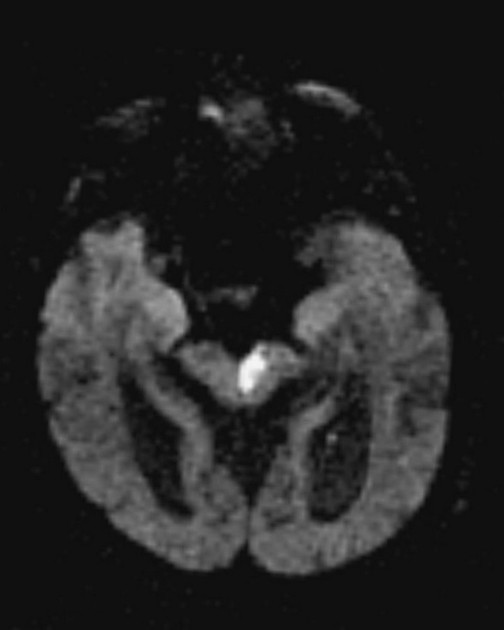

infarto isquêmico paramediano do mesencéfalo